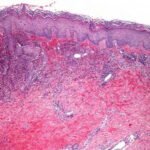

Histopathology. Typically, a dense perivascular infiltrate composed largely of neutrophils is seen assuming a bandlike distribution throughout the papillary dermis . Some of the neutrophils may show nuclear fragmentation (leukocytoclasis). In addition, the infiltrate may contain scattered lymphocytes and histiocytes and occasional eosinophils. The density of the infiltrate varies and may be limited in a small proportion of cases. Vasodilation and swelling of endothelium with moderate erythrocyte extravasation and prominent edema of the upper dermis are characteristic. In some instances, subepidermal blister formation may result. Extensive vascular damage is not a feature of Sweet’s syndrome. The histologic appearance varies depending on the stage of the process. In later stages, lymphocytes and histiocytes may predominate. Sweet’s-like neutrophilic dermatoses often show a similar histologic picture. However, the reaction pattern may on occasion be quite different, for instance, manifesting as deep subcutaneous localized suppurative panniculitis. The infiltrate of Sweet’s syndrome is not characteristic enough to exclude infection on histologic findings alone. As always, to arrive at the correct interpretation of a neutrophilic infiltrate, cultures need to be obtained and special stains need to be performed to exclude an infectious etiology. |